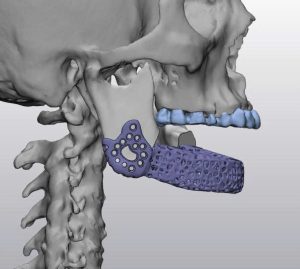

Hình ảnh trên minh họa quá trình thiết kế mô hình implant xương hàm dưới dựa trên dữ liệu CT-Scan. Các bác sĩ và kỹ sư sử dụng phần mềm chuyên dụng để:

Tái tạo cấu trúc xương 3D từ dữ liệu hình ảnh y khoa.

Thiết kế implant cá thể hóa: implant được tối ưu về hình dạng, độ dày, và lỗ thoát nhằm tăng cường sự tích hợp sinh học và lưu thông máu.

Mô phỏng phẫu thuật: cho phép bác sĩ xem trước kết quả phẫu thuật, giảm rủi ro và thời gian mổ.

Nhờ công nghệ in 3D, các mô hình implant được chế tạo với độ chính xác đến từng milimet, hỗ trợ phục hồi chức năng nhai và thẩm mỹ cho bệnh nhân sau phẫu thuật tái tạo xương hàm.